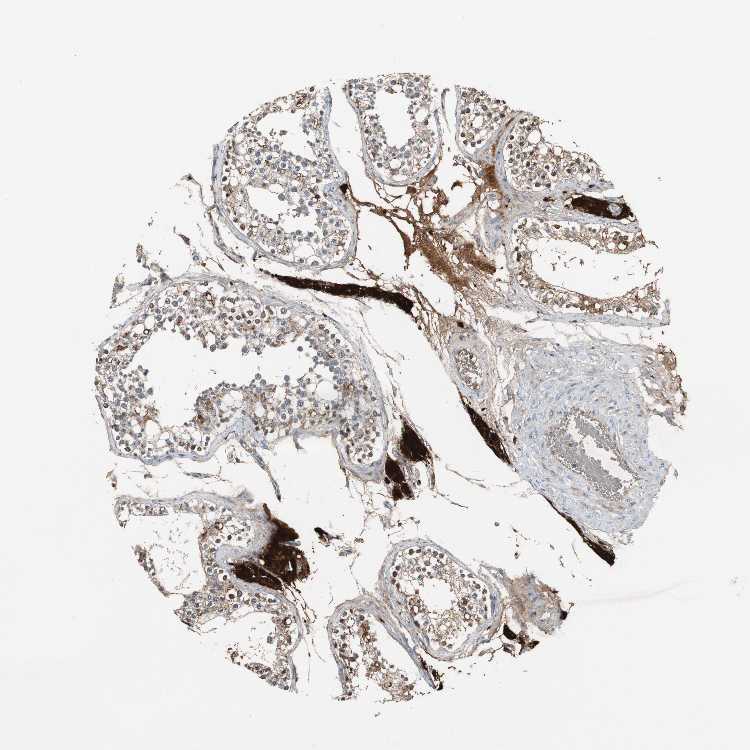

TESTIS - Antibody stainingi

Antibody staining in the annotated cell types in the current human tissue is reported as not detected, low, medium, or high, based on conventional immunohistochemistry profiling in selected tissues. This score is based on the combination of the staining intensity and fraction of stained cells.

Each image is clickable and will lead to virtual microscopy that enables deeper exploration of all samples and also displays staining intensity scores, fraction scores and subcellular localization as well as patient and tissue information for each sample.

Antibody HPA007305Antibody HPA007306Antibody CAB000106

Leydig cells HighHighHigh

Cells in seminiferous ducts Not detectedMedium-